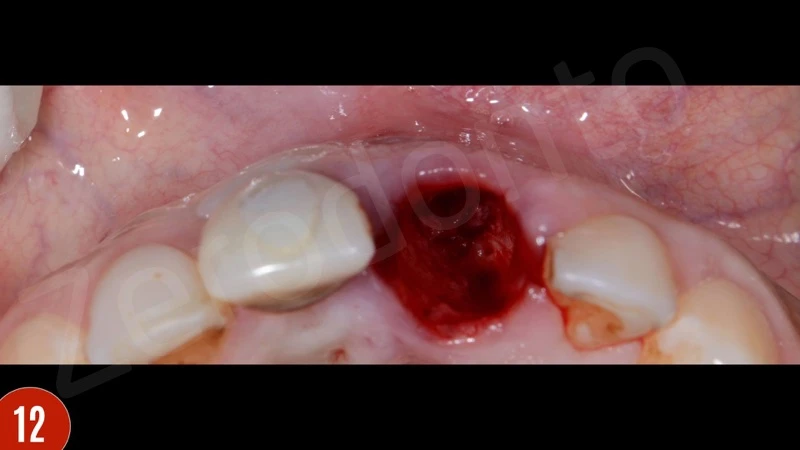

Sự lành thương sớm và tăng độ dày niêm mạc phía môi là thích hợp. Ba tháng sau khi phẫu thuật nha chu, bệnh nhân báo cáo có lỗ rò ở vùng đỉnh răng 21. Đo độ sâu thăm khám là 2-3 mm. Do răng không vừa khít, và lực nhai quá mức, một gãy xương ở vùng chóp đã gặp phải. Bệnh nhân được giải thích cần nhổ răng. Bệnh nhân đã quyết định cấy ghép tức thì.

Sau khi nhổ răng, mô hạt đã được loại bỏ cẩn thận. Khoan xương phía khẩu cái cung cấp sự ổn định chính và đặt phục hình tạm thời. Để bảo vệ các đường cong phía môi, khoảng trống giữa bản xương phía môi và implant được ghép với xương bò khử khoáng. Phục hình tạm thời được gắn vào implant tại lực torque 15 Ncm.